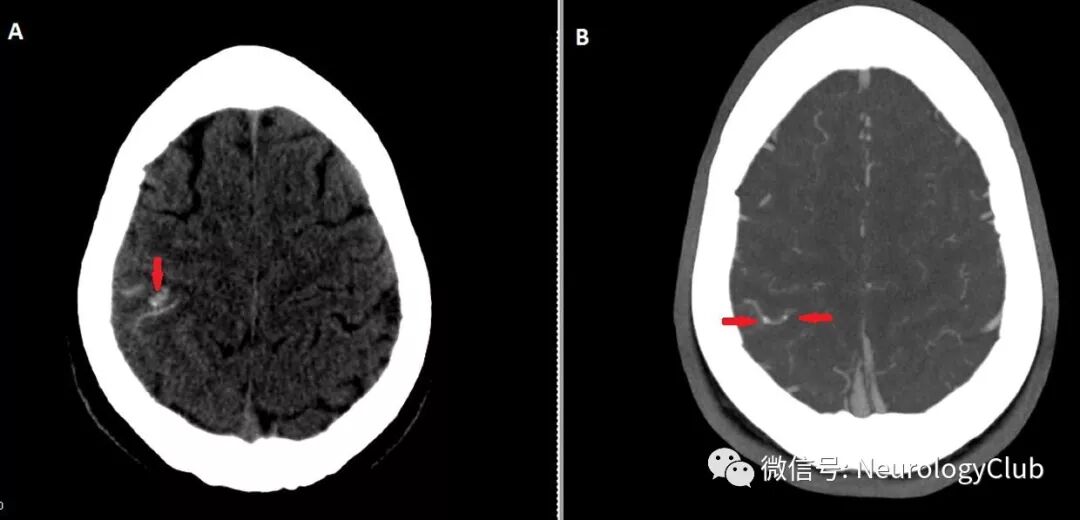

(图3:A:经食道心超提示二尖瓣赘生物;B:经食道心超提示二尖瓣赘生物内可见钙化

患者表现为凸面蛛网膜下腔出血伴出血区和动脉内小钙化灶(图1)。进一步查体可闻及新发较响的收缩期杂音。给予经验性抗感染性心内膜炎治疗。4小时后患者症状恶化,出现表达性失语。复查影像学可见新发钙化病灶和缺血性卒中(图2)。超声心动图提示二尖瓣赘生物伴钙化(图3)。血培养可见副血链球菌生长。